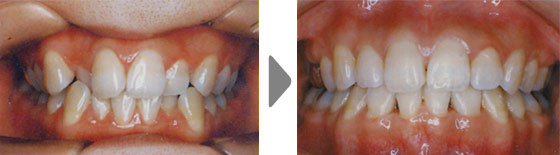

審美の改善

上顎前突(出っ歯)、下顎前突(受け口)や叢生(でこぼこの歯列)は笑った時の見た目はもちろん、口を閉じた顔貌の調和も乱れてしまいます。